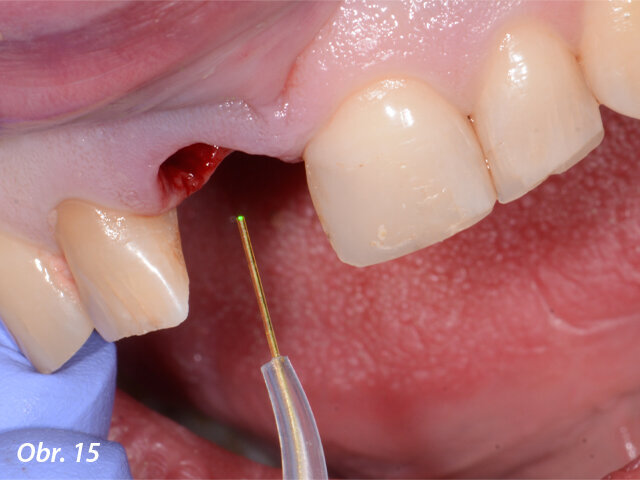

Dezinfekce poextrakčního lůžka použitím laseru Nd:YAG Fotona.

Po atraumatické extrakci zubu 11 bylo možno díky laseru Fotona LightWalker důkladně očistit lůžko zubu od zánětlivé tkáně vzniklé vlivem chronického zánětlivého stavu. Dále byla provedena dezinfekce lůžka zubu laserem Nd:YAG. Implantát byl zaveden ve správné, předem naplánované, pozici s použitím chirurgické šablony vytištěné v Belgii ze speciální lékařské pryskyřice (s možností sterilizace výrobku před výkonem). Po sejmutí šablony byla našroubována korunka spolu s abutmentem (cementováno předem mimo ústa pacienta) do implantátu a dále byla provedena fotomodelace tkání laserem Nd:YAG s cílem získání lepšího a rychlejšího hojení. Kontrolní CBCT vyšetření ukázalo ideální lokalizaci implantátu vzhledem k plánované pozici.